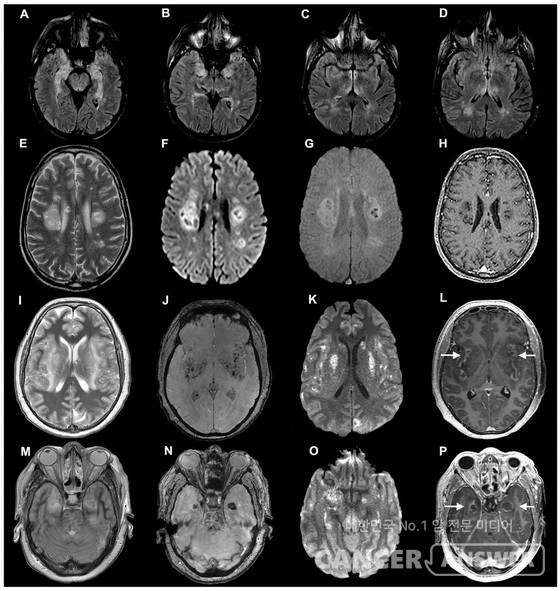

이와사키 박사의 연구팀은 코로나19로 사망한 환자의 뇌 조직, 실험 쥐, 오가노이드(뇌 구조를 모방한 실험용 뇌세포 클러스터)를 이용해 뇌세포에 침투한 코로나19 바이러스의 행동을 관찰했다. 그 결과, 코로나 바이러스에 감염되면 두뇌의 신경세포(뉴런)을 연결하는 시냅스의 양이 많이 줄어들었다.

해당 연구가 진행되기 전에 상당수의 코로나 바이러스 확진자가 어지러움과 섬망 및 망상 등의 뇌 이상 증상을 보고했었다. 아직까지는 이런 증상이 직접적인 뇌 손상 때문인지 코로나19 바이러스의 합병증 때문에 일어난 증상인지는 정확하게 밝혀진 바 없다. 하지만 지금까지 의학계에서는 코로나19 바이러스는 두뇌를 침투하기 어렵다는 의견이 일반적이었는데 해당 연구로 인하여 코로나19 바이러스가 뇌도 감염할 수 있다는 가능성이 제시됐다.